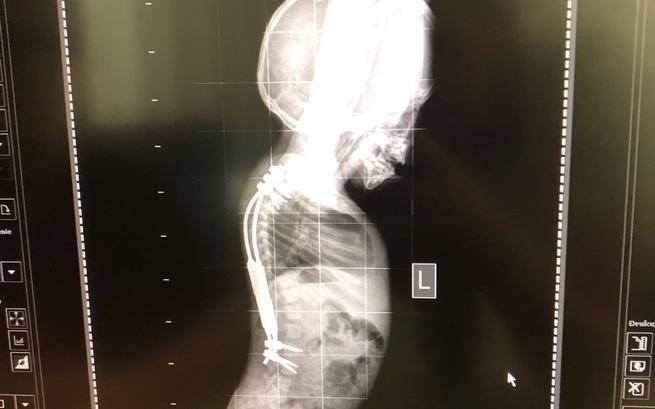

Last summer, Adaś underwent a very complicated spinal surgery. We spent over 6 weeks in the hospital. First, his spine was straightened on a specially prepared extract with the HALO ring and then a special growing bar system was implanted. The results are great. We managed to fund this operation in cooperation with the NFZ.